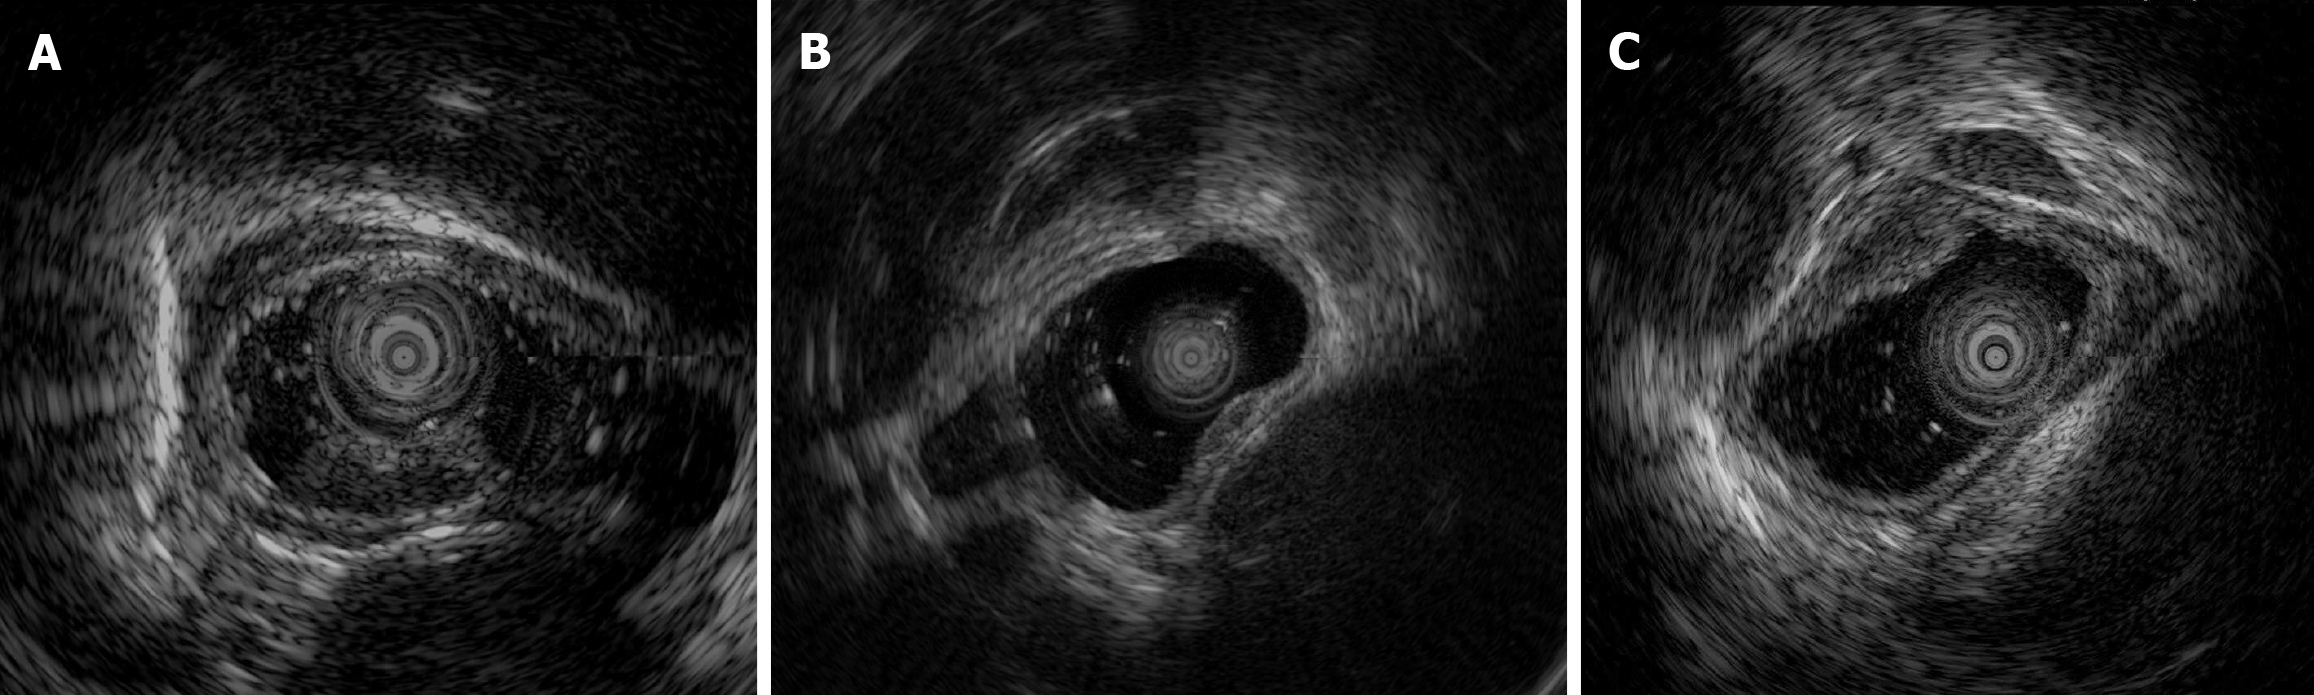

EUS was routinely performed according to well-acknowledged procedures using an Olympus EU-ME2 (Olympus Corporation, Tokyo, Japan) and mini probe with a frequency of 12 MHz. Among the patients with early E-NEC, three underwent EUS (Figure 3), which revealed solitary hypoechoic lesions originating from the muscularis mucosae or submucosa with homogeneous internal echogenicity, clear borders, normal peripheral esophageal hierarchical architecture, and intact muscularis mucosae and epithelial membranes. In one patient, multiple enlarged lymph nodes were observed outside the esophageal wall. The average grayscale value of EUS images for early E-NEC (n = 3) was significantly higher than that of esophageal leiomyoma [n = 8, 63.79 ± 1.42 vs 49.44 ± 11.57, P = 0.01, Cohen’s d = 1.402; 95% confidence intervals (CI): -0.2718 to 3.077], indicating that early E-NEC lesions exhibited higher echogenicity than esophageal leiomyomas (Figure 4).